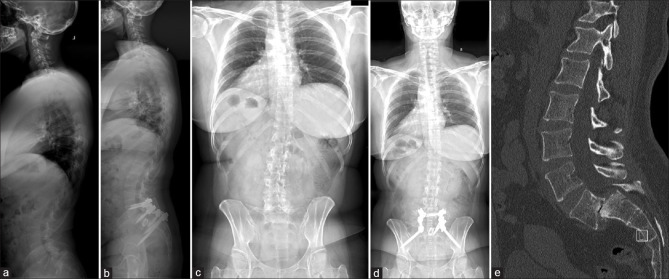

High-grade spondylolisthesis (HGS) remains a difficult entity to treat, given the high rate of complications following surgical correction of such a spinal deformity. Reduction of spondylolisthesis may be associated with traction injury to the L5 nerve root due to stretching. We report on two cases of HGS where a novel surgical technique of offset rods was used for partial reduction of spondylolisthesis thereby reducing L5 nerve root traction. Both cases had more than 50% correction of translation with good correction of slip angle and satisfactory clinical outcomes were achieved at the final follow-up. In this study, we report on two cases of HGS treated with offset rod constructs. These rod constructs provide partial reduction, improving slip angle at the listhesis while reducing nerve root stress caused by full reduction and fixation. In comparison to previously described constructs, offset rods provide greater construct modularity and freedom to create constructs better suited to each patient's pathology.